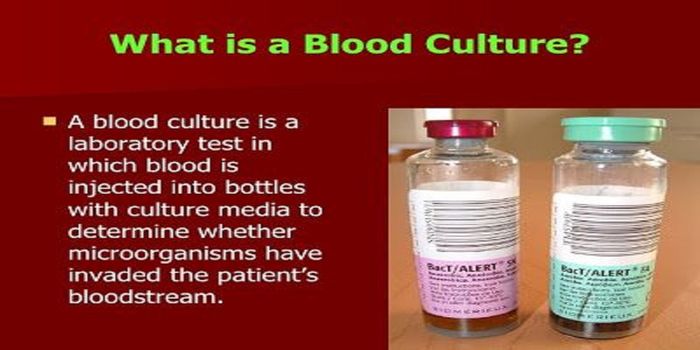

FEB 20, 2019Health & MedicineConventional methods of identifying a positive blood culture require waiting for the blood culture broth to grow th ...

FEB 23, 2019Health & MedicineFacklamia species are Gram-positive, facultatively anaerobic bacteria that present a challenge for clinical labs to ...